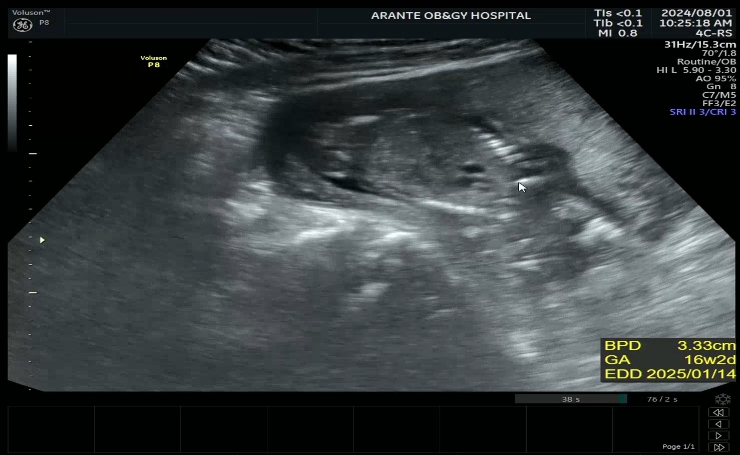

28w 1d 정기검진

2024.12.19

입체초음파 찍는날 세상에 첫째랑 완전 똑같 애기가 태반에 얼굴을 파묻고 있어서 보기가 매우 힘들었는데 ...